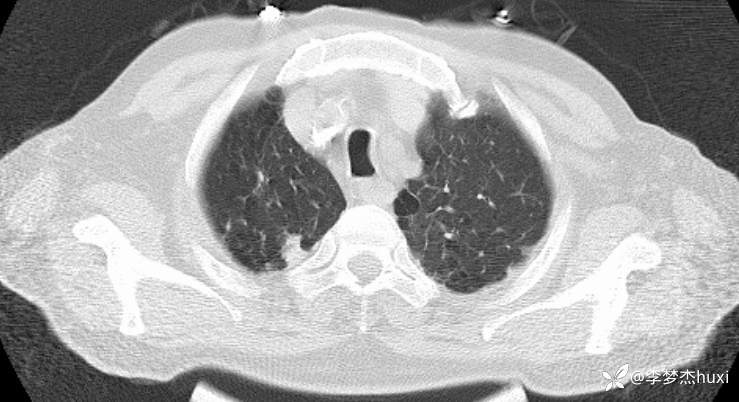

男, 82 岁,主因慢性咳喘20余年,患慢阻肺,平时喘息药物维持,半年前反复住院,并因为病重转上级医院治疗,自诉回家后做梦梦到自己换了一个狗肺,感觉从此不再喘息。